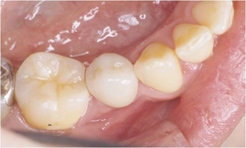

審美インプラント治療(こだわりのインプラント治療)右下小臼歯部

右下小臼歯部

両隣りの歯を削らずにインプラント治療を行いました。

- インプラント(1本)

- ソケットプリザベーション

- インプラント上部セラミック冠 (1本)